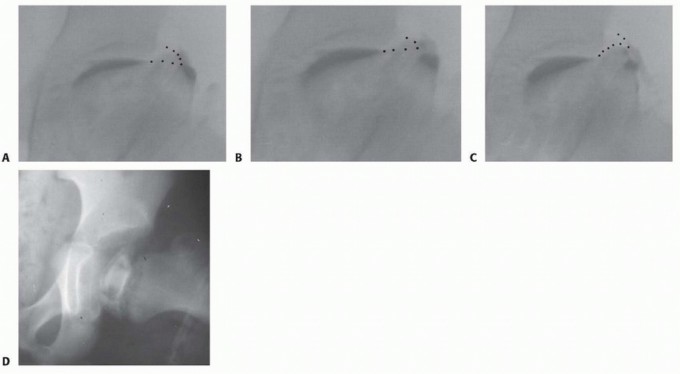

Arthrography is performed to verify reduction of the subluxation and femoroacetabular impingement.

With the arthrographic dye in the hip joint, the degree of femoral epiphyseal deformity and subluxation is observed with the image intensifier.

The leg is then abducted and the area of hinge abduction is observed.

In many cases, the deformed femoral head will press against the lateral margin of the labrum and block the reduction of the femoral head into the acetabulum ( TECH FIG 1A-C ).

--- TECH FIG 1 • A-C. Arthrograms of the hip of a patient with Perthes disease in which the leg is progressively abducted. The abnormal femoral head deforms the labrum with progressive abduction of the leg. D. AP radiograph of the hip of a patient with Perthes disease in which the femoral epiphysis is contained within the acetabulum as the leg is placed in abduction.

The arthrographic dye will pool in the medial-inferior joint, and with additional attempted abduction of the leg, the lateral margin of the labrum will deform upward.

In these cases, an adductor muscle tenotomy is then performed through a medial adductor incision.

Afterward, the leg is again abducted to determine if the hinged abduction has been corrected (ie, reduction of the weight-bearing surface of the femoral epiphysis within the acetabulum).

The hip is considered to be reduced if the deformed part of the femoral head (weight-bearing area) is under the lateral margin of the acetabulum (contained within the acetabulum), the medial dye pool is reduced, and the lateral margin of the labrum is not deformed.

If the hip reduces (

TECH FIG 1D

), proceed with the shelf procedure as described in the following section.